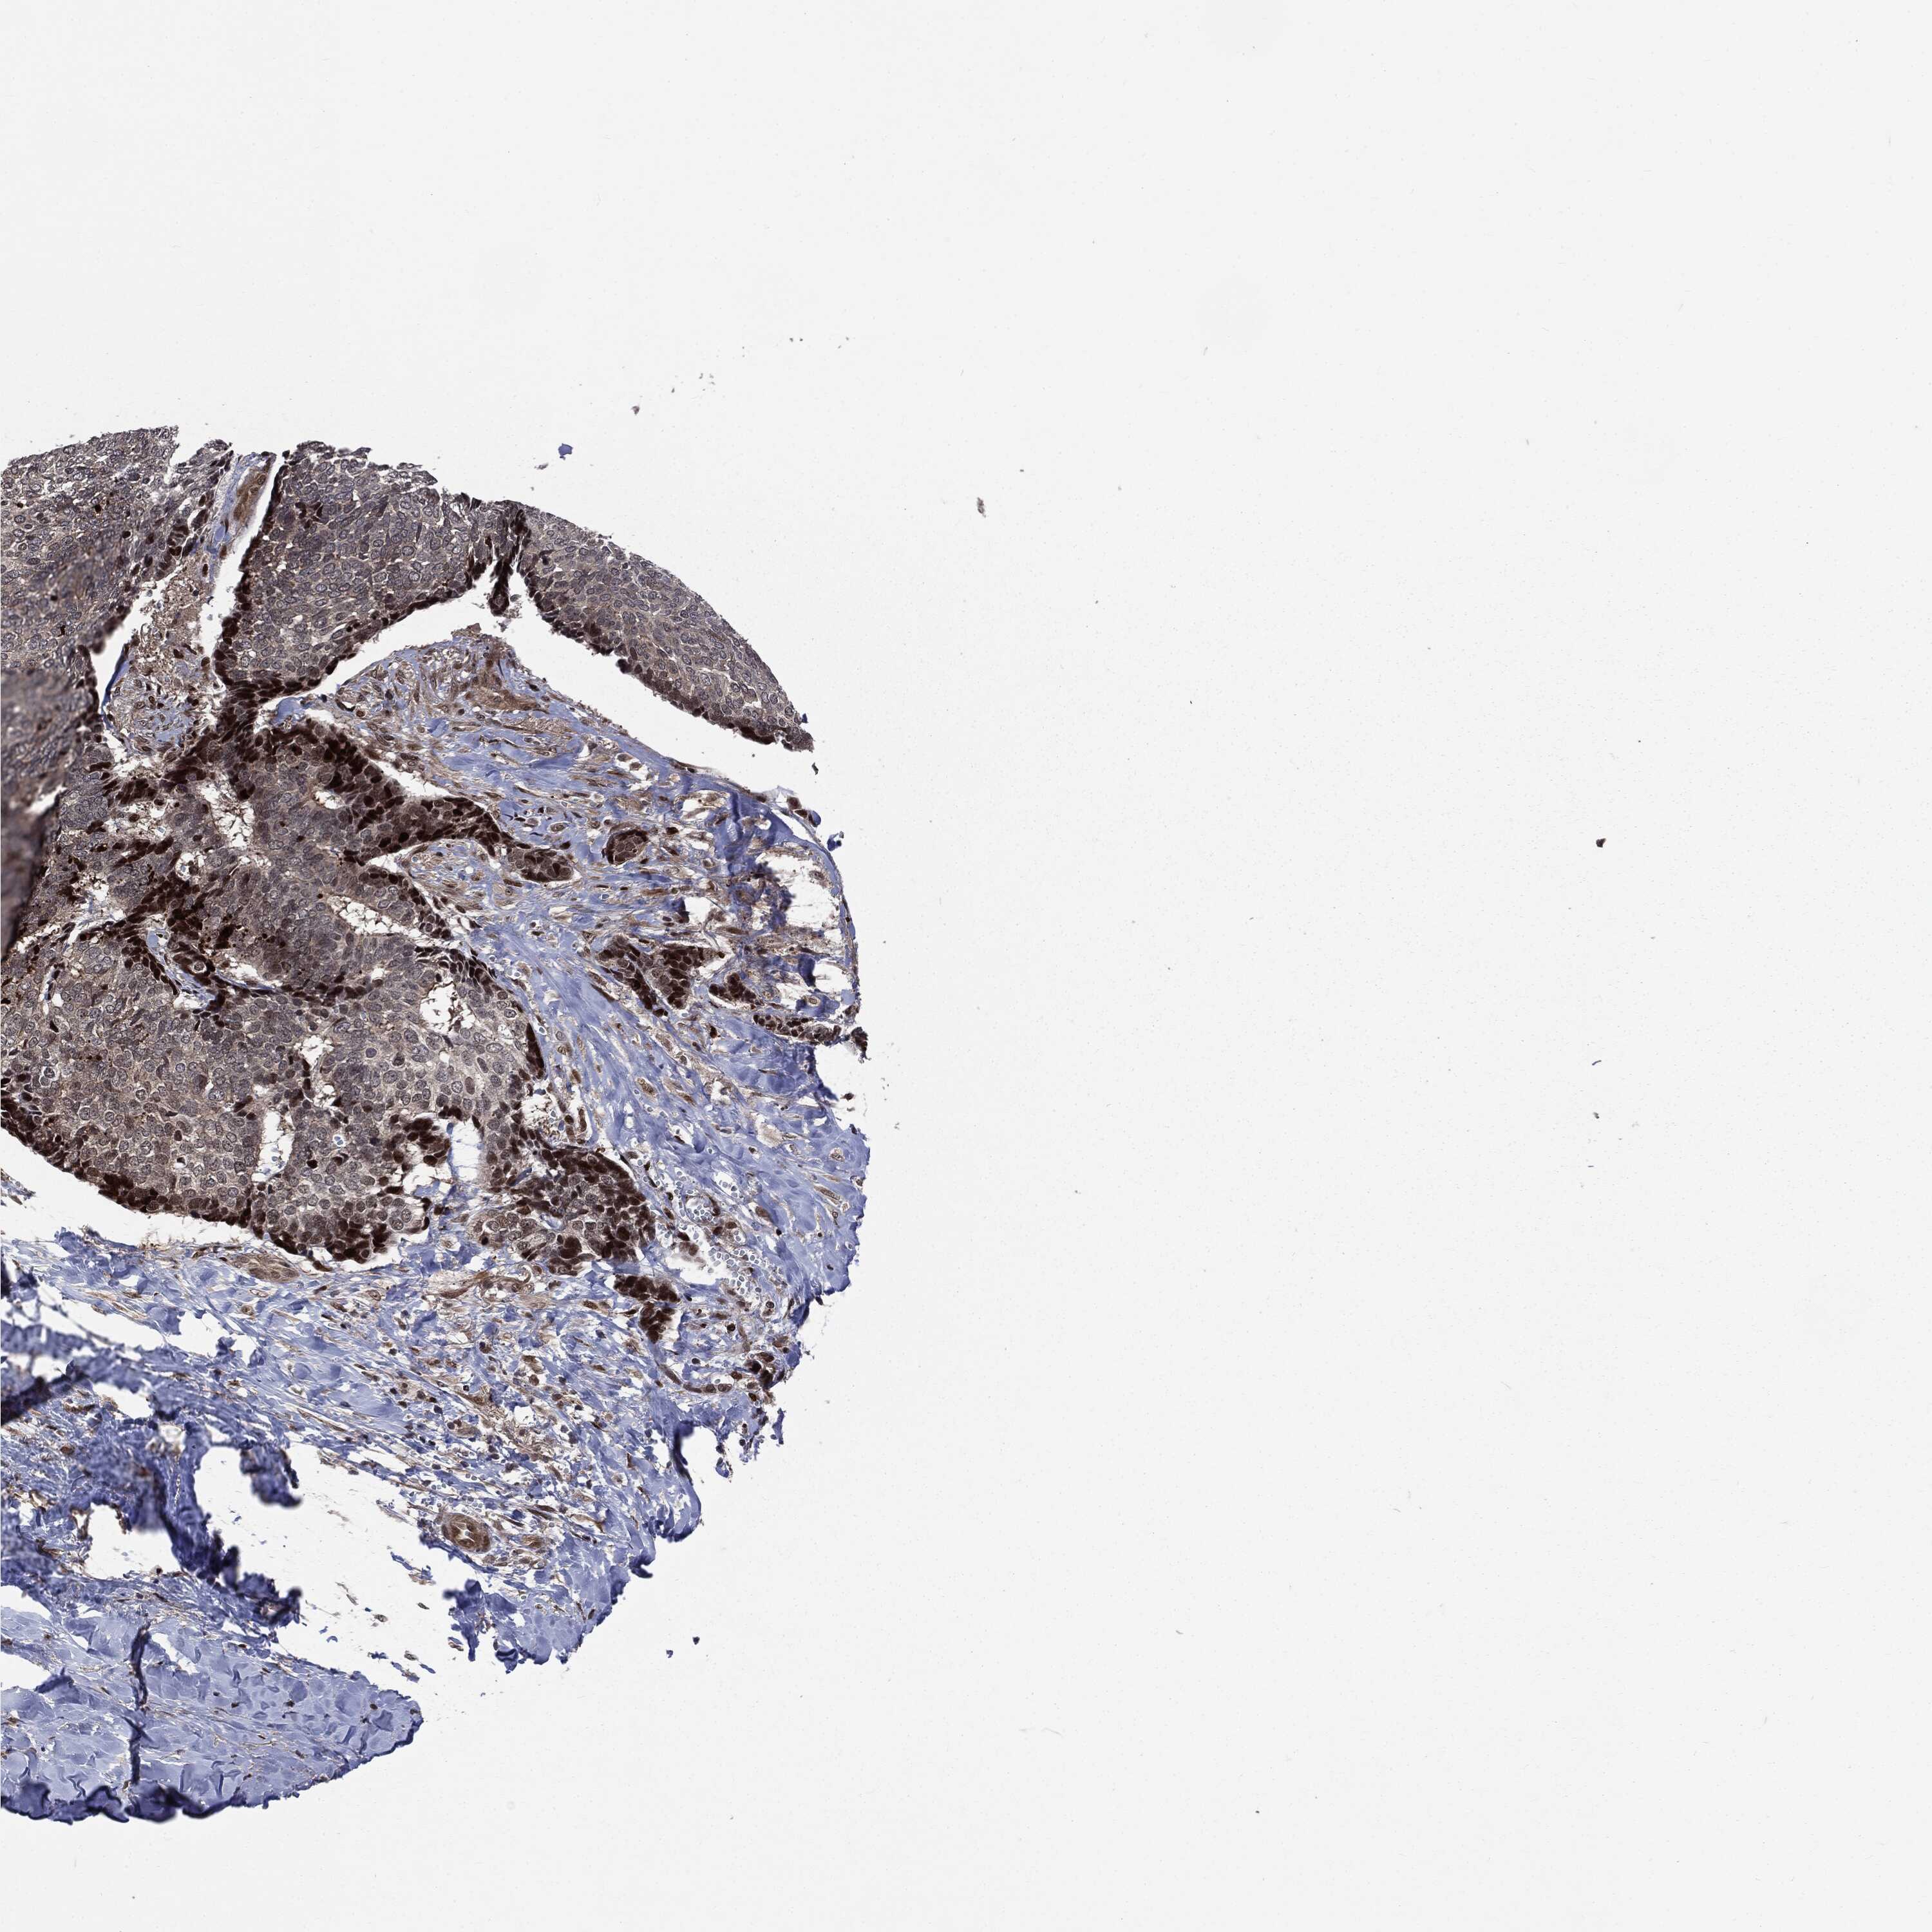

SKIN CANCER - Protein expressioni

A mouse-over function shows sample information and annotation data. Click on an image to view it in a full screen mode. Samples can be filtered based on level of antibody staining by selecting one or several of the following categories: high, medium, low and not detected. The assay and annotation is described here.

Antibody stainingi

Antibody staining in the annotated cell types in the current human tissue is reported as not detected, low, medium, or high, based on conventional immunohistochemistry profiling in selected tissues. This score is based on the combination of the staining intensity and fraction of stained cells.

Each image is clickable and will lead to virtual microscopy that enables deeper exploration of all samples and also displays staining intensity scores, fraction scores and subcellular localization as well as patient and tissue information for each sample.

Antibody CAB080136

Squamous cell carcinoma, NOS

Squamous cell carcinoma, metastatic, NOS